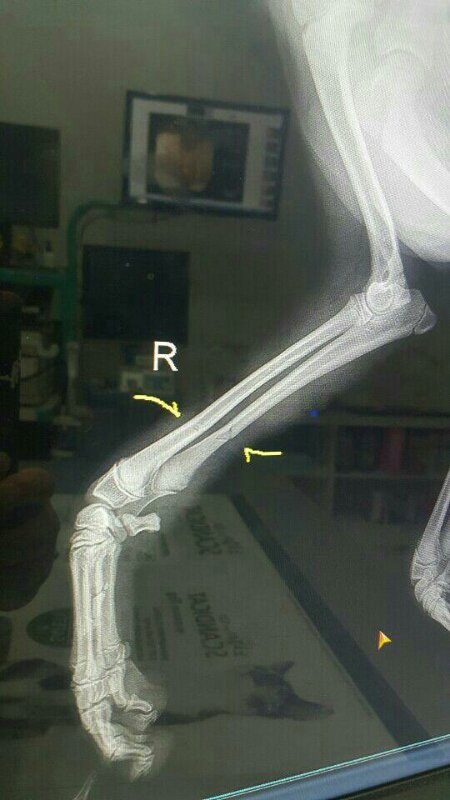

차를 돌려 2차선에 누워있는 아이를 조심히 갓길로 옮기고 상태를 보니 앞다리 하나가 덜렁거리고 입에 출혈이 나고 있었습니다.

다급히 병원으로 옮겨 검사결과 앞다리 골절과 턱에 금이간 상태였습니다.

바로 응급수술을 했고 지금은 회복하고 중성화까지 맞혔습니다.